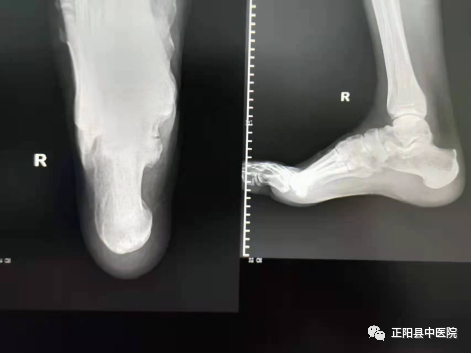

是不是所有的正侧位DR片搭配都能够给临床提供更多的信息呢?其实不然,在实际工作中我们还会遇到正侧位或侧轴位如此完美搭配,还依然不能诊断出来的外伤性骨折如下图。

这是一次夜班急诊中遇到的真实病例,跟骨侧轴位搭配如此完美,可是找不到异常征像,病人的足踝部肿胀非常明显,疼痛难忍。我们的外科医生经过与病人认真沟通后,做了一个64CT扫描,发现了跟骨的骨折。